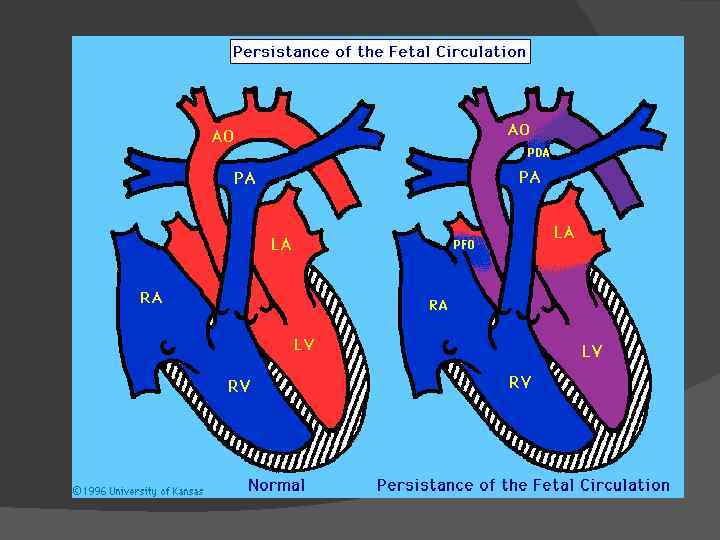

Пренатальный период Во внутриутробном периоде основная масса крови, поступающая из правого предсердия в правый желудочек и легочную артерию, попадает не в легкие, а через артериальный проток в аорту.

После рождения артериальный проток облитерируется. Это связано с тем, что изменяется соотношение органов средостения и при расширении легких проток, натянутый между легочной артерией и аортой, перегибается. Кроме того, на закрытие артериального протока влияет изменение химического состава крови.

Этиология В некоторых случаях, причина которых неясна, проток не закрывается и остается сообщение между аортой и легочной артерией. Частота этого порока довольно велика и составляет 10 -25% всех врожденных сердечных аномалий. У женщин порок встречается чаще (7080% случаев)